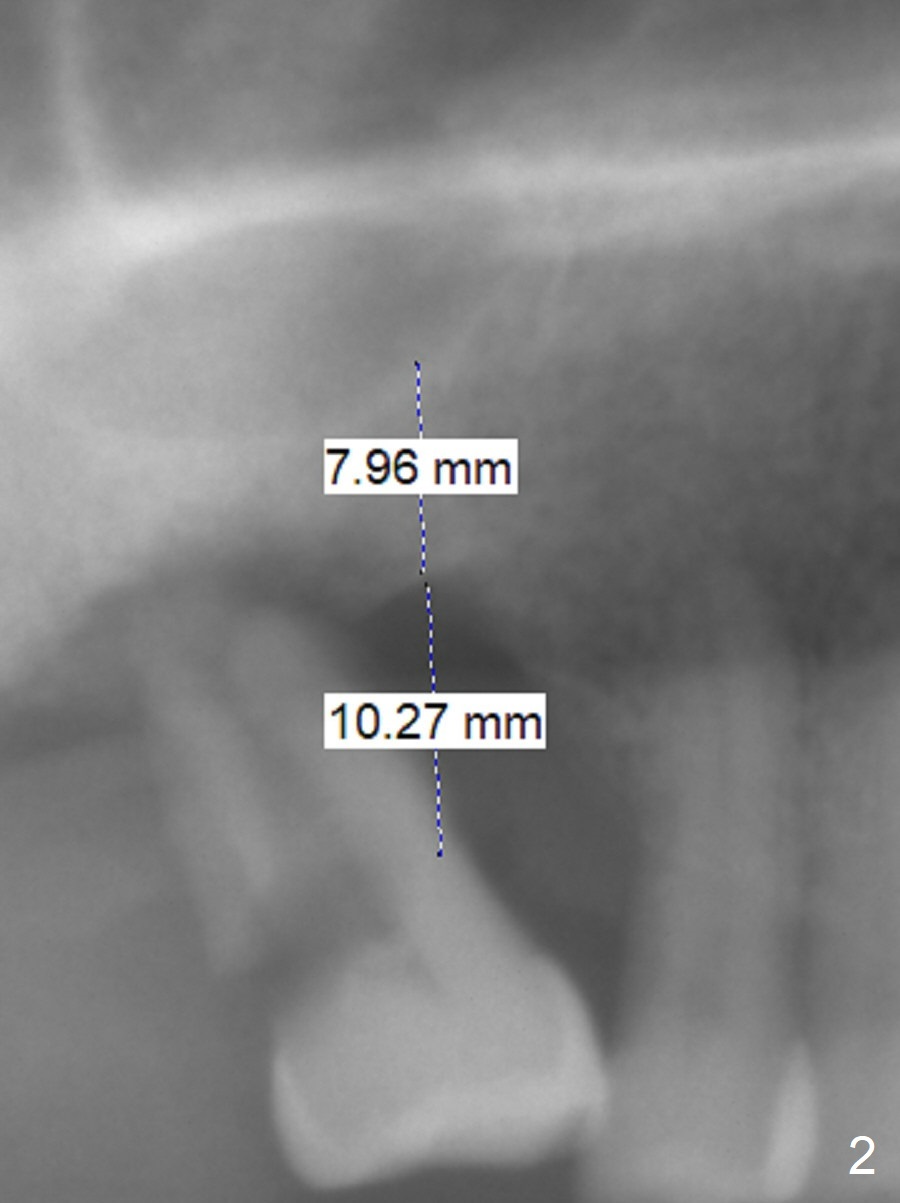

A 53-year-old man has severe peridontitis (Fig.1). The tooth #3 has exfoliated. The 1st implant will be placed at #3, where the gingiva seems to be thick (Fig.2: 10 mm). A mill abutment will be used.